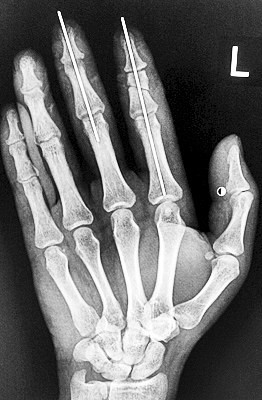

术后X光显示,骨骼对位良好。

最终,卢微波和团队找好了需要的血管和神经,做好标记后,开始固定食指骨骼、吻合肌腱,最后在显微镜下用直径20微米的无创显微缝合线开始吻合血管和神经。

在经过两个多小时手术后,早上8时许,卢微波下令松止血带,数十秒后男子苍白的食指逐渐红润起来,食指在离体10个小时后恢复血运。

紧接着,卢微波又开始中指再植手术。上午10时许,中指在离体12小时后也成功恢复血运。